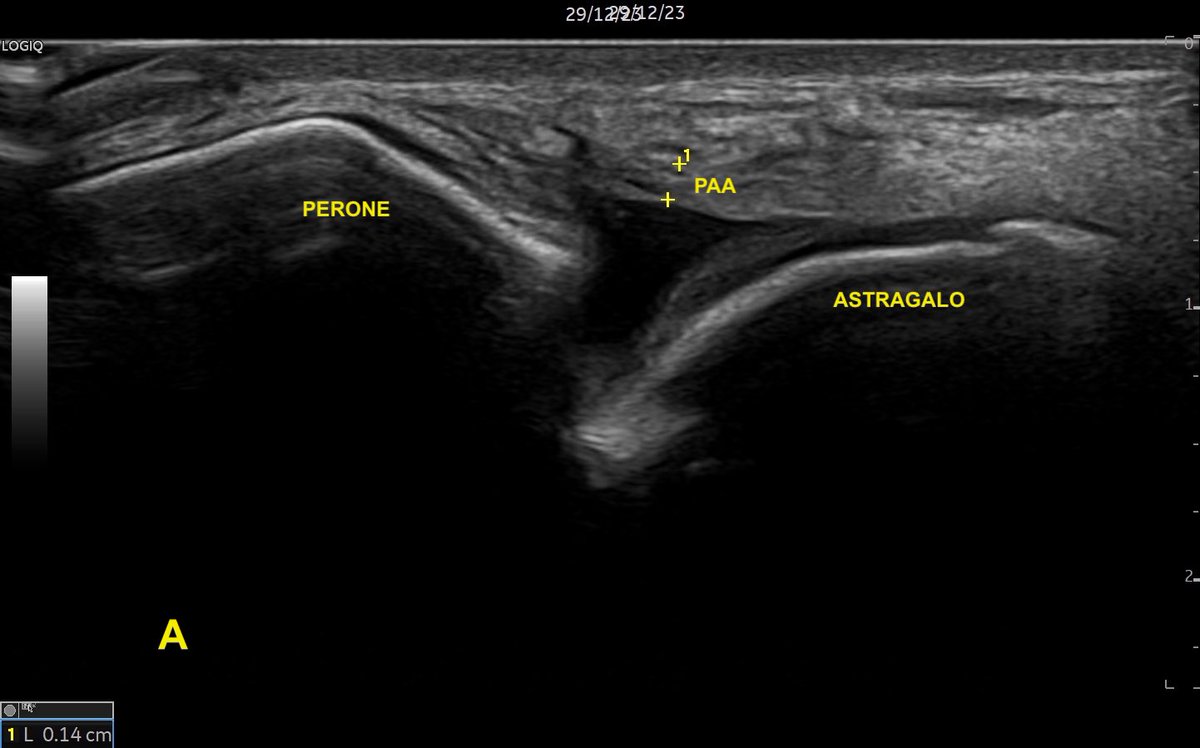

Tobillo inestable: #ecografia del fascículo peroneo astragalino anterior roto parcialmente. Imagen A, ligamento roto en su mayor parte (grosor 1.4mm). Imagen B del mismo ligamento: área conservada con un grosor de 3.3mm. Conclusión: siempre escanear toda la amplitud del ligamento